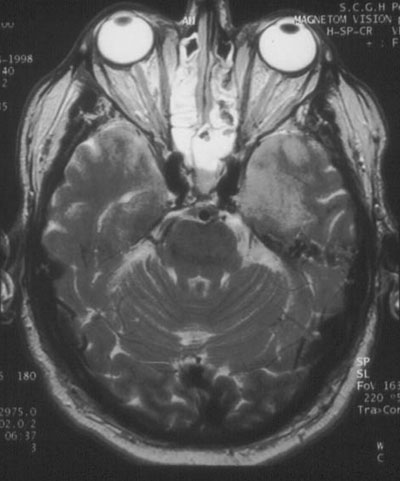

8: Case report — sudden onset of seizures and loss of consciousness

Presentation: A 70-year-old man was taken to a hospital emergency department in a comatose state. He had become ill very suddenly while talking on the telephone — stopping in mid-sentence and having a generalised seizure.

Examination: The patient had a Glasgow Coma Score of 3, which did not respond to intravenous glucose or phenytoin. Initial computed tomography revealed no haemorrhage or focal lesion.

Management: He was admitted to the intensive care unit, ventilated and treated with intravenous aciclovir.

Investigations: Initial analysis of the cerebrospinal fluid (CSF) showed 7 x 106 lymphocytes/L; no red blood cells; protein level, 0.61 g/L; glucose level, 9 mmol/L and CSF : serum ratio, 80%. CSF was negative for cryptococcal antigen and, on polymerase chain reaction testing, for enteroviruses and Murray Valley encephalitis virus, but positive for HSV-1. An electroencephalogram showed periodic lateralising epileptiform discharges in the left temporal lobe. Magnetic resonance imaging on Day 4 showed bilateral temporal lobe abnormalities (Figure).

Diagnosis: Encephalitis caused by herpes simplex virus (HSV).

Course and outcome: Aciclovir treatment was continued, and the patient's condition improved gradually after successful treatment of complications that included aspiration pneumonia. He was transferred from the intensive care unit on Day 21. Although the patient's rehabilitation was complicated by inappropriate behaviour and memory disturbance, he was able to be discharged home on Day 50.

Features suggesting encephalitis were cortical signs (coma and seizure) and cerebrospinal fluid profile (Box 3).

Patients presenting with encephalitic syndromes should receive empirical therapy with aciclovir to cover the possibility of HSV infection until an aetiological cause is identified.

Temporal lobe sequelae (memory disturbance and behavioural abnormality) are characteristic of HSV encephalitis.